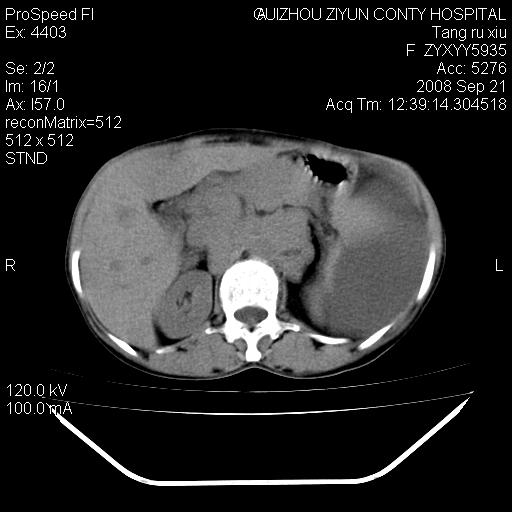

f、57岁,上腹痛.2月,近来胸闷。2月前在外院摄胸片示左侧胸腔少量积液。

(患者腹痛入院,欲吐,临床医生说禁饮,所以没有口服对比剂)

肝脏大小形态尚可,其实质内可见多发大小不等的低密度影,边缘模糊。肝门区结构紊乱,腔静脉腹主动脉旁可见多发软组织密度影,部分融合成团块状,并向下延伸。胰腺及十二指肠结构显示不清。腹腔内脐后肠管走形僵硬,管壁可见增厚。盆腔内可见多个淋巴结影。所扫层面左侧胸腔可见大量弧形水样密度影,其内侧可见被压缩的肺组织影。左侧胸壁可见一小结节样软组织密度影,边缘模糊。心脏纵隔向右侧移位。心脏包膜内可见囊样低密度影,其内侧心房室周围可见一圈气体样密度影。纵隔内大血管旁可见多发软组织团块影,部分融合。

1.腹膜后淋巴瘤侵及肝脏,肺内及纵隔内多发转移。2.左侧大量胸腔积液并压缩性肺不张。3.心包脓肿可能,转移不除外。4.脐后局部肠管管壁增厚,考虑炎症可能,肿瘤不除外。